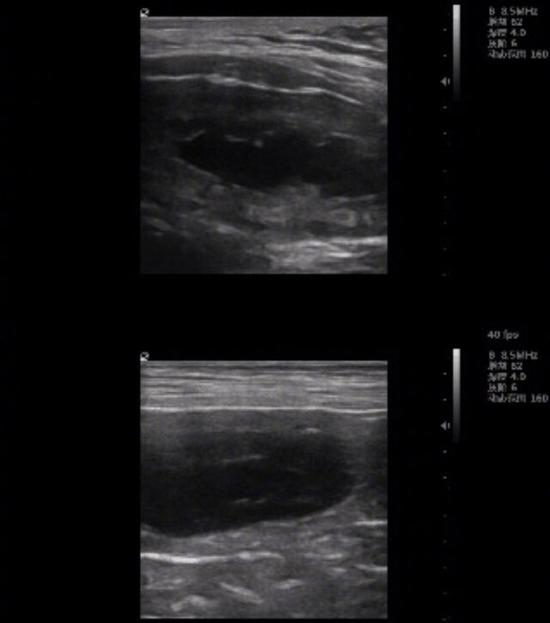

4月6日,小马甲发布了一条微博,称:“一件开心的小事:妞妞怀孕了!刚拿到结果,宝宝的形态数量这些要等过些日子复检才知道。

妞妞目前怀胎状况还不明确,希望母子平安吧,以后有小妞妞和大妞妞一起出镜了!